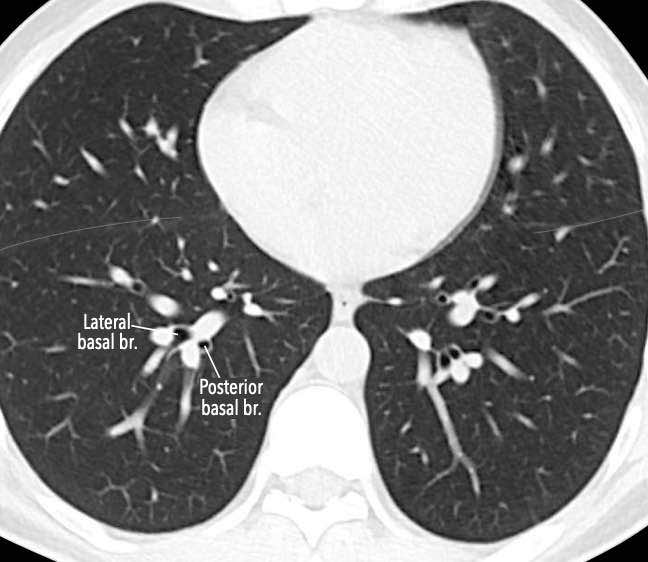

Phế quản trên CT

Cuộn qua các hình ảnh để quan sát khí quản phân chia thành phế quản chính phải và trái, sau đó tiếp tục phân chia thành các phế quản thùy và phế quản phân thùy.

Các phân thùy phổi trên CT

Cuộn qua các hình ảnh để quan sát cách phổi được phân chia thành các phân thùy.